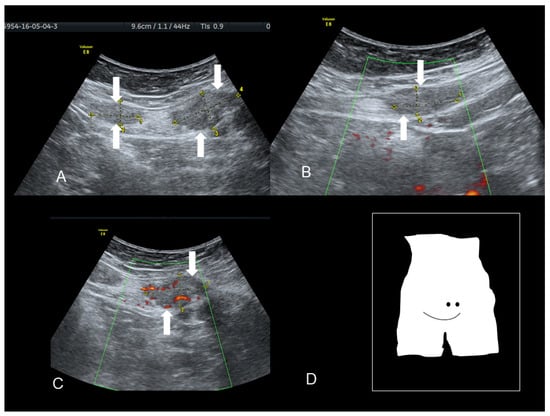

Figure 6. The ultrasonographic appearance of a rectus abdominis endometriotic nodule (see white arrows) (AD) in a woman with previous cesarean section and hysterectomy. The last picture (D) is taken during the needle biopsy.

Endometriosis of the rectus muscle is an extremely rare localization of extra-pelvic endometriosis [19]. Ultrasonography usually demonstrates a heterogeneous hypoechogenic formation with indistinct edges [20] (Figure 6, Figure 7 and Figure 8). To help in the diagnosis, if the patient moves her legs alternatively during the examination the operator can easily visualize the muscular layers.